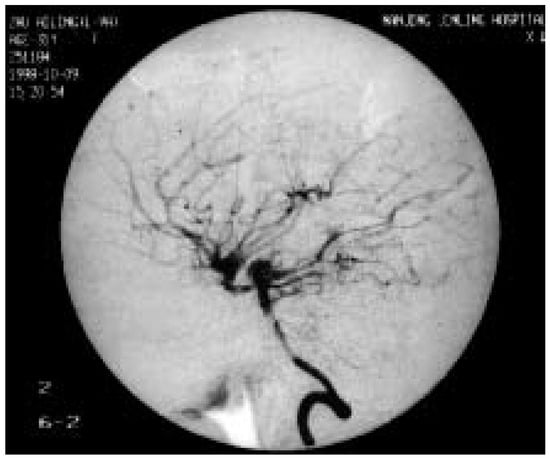

Rarely, adult moyamoya disease presents with recurrent migraine-like headaches during a long course.We report the case of a 31-year-old woman with moyamoya disease and migraine-like headaches, with a 13-year history. Physical examination showed no neurologic deficits. Magnetic resonance angiography (MRA) and digital subtraction [...] Read more.

Rarely, adult moyamoya disease presents with recurrent migraine-like headaches during a long course.We report the case of a 31-year-old woman with moyamoya disease and migraine-like headaches, with a 13-year history. Physical examination showed no neurologic deficits. Magnetic resonance angiography (MRA) and digital subtraction angiography (DSA) showed occlusion of the right internal carotid artery (ICA), severe stenosis of the left ICA, and abnormal vascular network at the base of the brain. The calcium channel blocker, nimodipine, was introduced in order to prevent further symptoms. After the introduction of nimodipine, no further headache, weakness and numbness of the left hand occurred in this patient. This suggests that migraine-like headaches may be caused by moyamoya disease and that nimodipine may have a beneficial effect on this condition. Full article